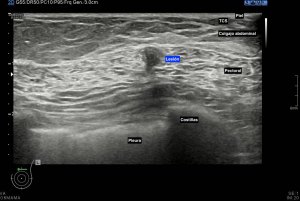

Los vientres anteriores de los músculos Digástricos, que son el objeto del desarrollo de este Post, son dos estructuras musculares redondeadas en el corte transversal, imagen 1, y alargados si los estudiamos en el eje largo, imagen 3, mira:

Ecográficamente los músculos digástricos en eje corto tienen semiología hipoecogénica, en aspecto de noche estrellada, como la de hoy, y en el eje largo en forma de penacho o en forma de plumas con las fibras alargadas y paralelas a la superficie.